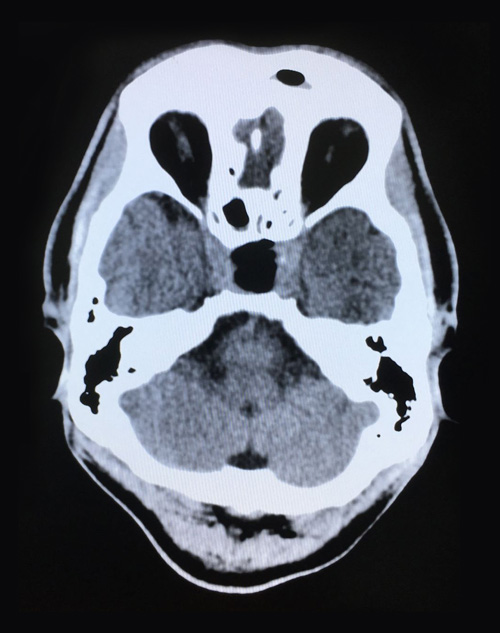

术后第二天影像:肿瘤切除干净,鞍内脑脊液填充